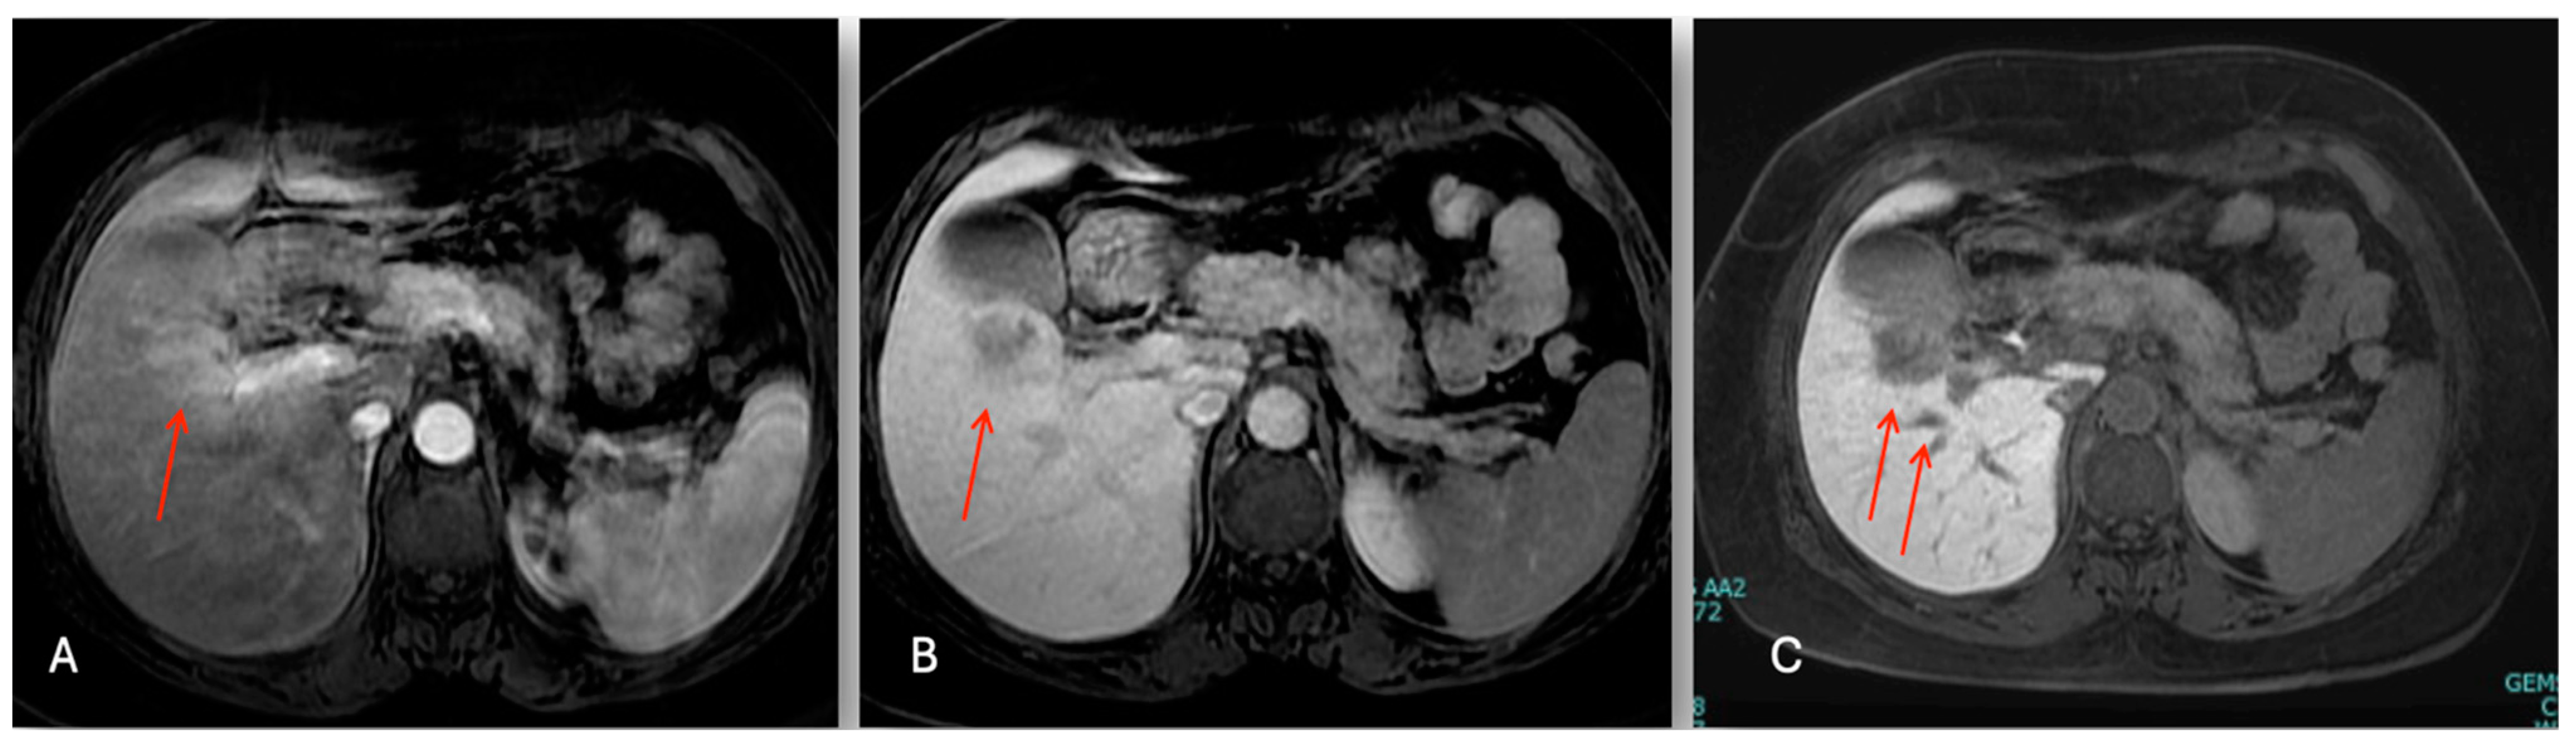

3.2.2. Case 2

The abdominal ultrasound showed a 36 × 28 mm hypoechoic lesion in S5 near to a normal gallbladder. The Gd-EOB-DTPA-enhanced magnetic resonance imaging (MRI) showed a 38 mm tumor in segment 5 with a low intensity on the T1-weighted images, and a light high intensity on the T2-weighted images and DWI (Figure 4). The abdominal enhanced CT scan (Figure 5) confirmed a nodule with enhancement in the arterial phase and washing out in the portal, which is highly suspect for mass forming cholangiocarcinoma versus fibro-lamellar HCC within a normal liver.

Figure 4.

Sequential dynamic contrast enhancement liver MR images. Nodule in S5 (red arrow): (A) hyper-intensity in T2 phase; (B) hypo-intensity in T1 phase; and (C) hypo-intensity in hepatobiliary phase.